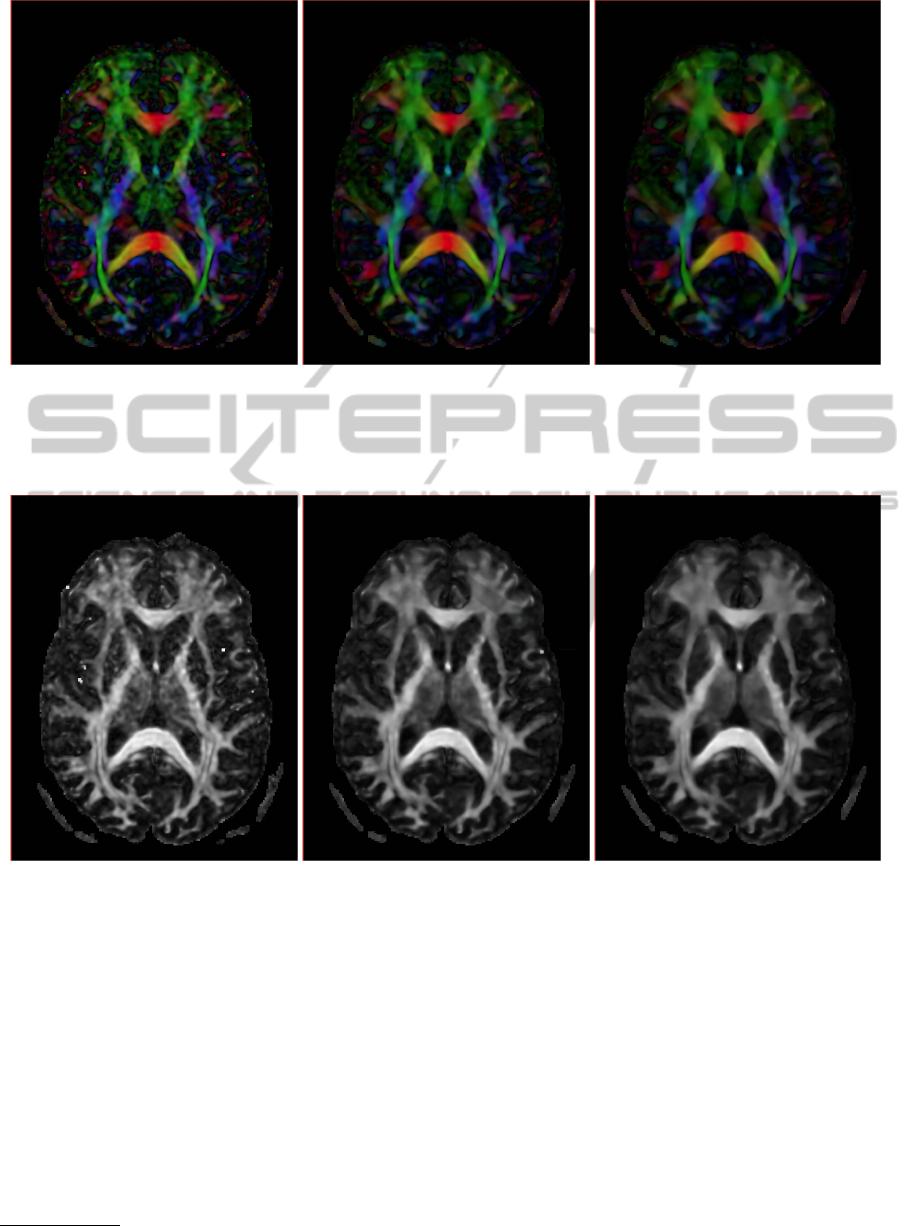

The effect of this denoising process over the re-

constructed tensor and their derived scalar measure-

ments (obtained with the 3d Slicer tools) is presented

in Figures 7 and 8. Figure 7 shows a color-coded

orientation map created from DTI data. In this im-

age, the principal colors (red, green, and blue) rep-

resent fibers running along the spatial orientations

(x,y, z). Results in 7 shows that the structures are

better defined if the DW-MRI volume is denoised

previously. As evidenced by Figure 8 this effect is

yet more visible in the measurements like the Frac-

tional Anisotropy where the structures and details are

clearly enhanced. When we use a lower value for λ

(Figures 7(c) and 8(c)) we obtain smoother tensorial

images but some details can be better distinguished

when the value of λ is higher (Figures 7(b) and 8(b)).